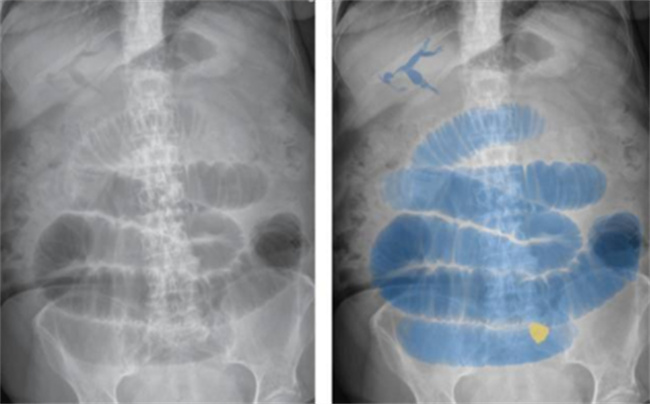

婴幼儿出现腹胀、腹泻、便秘、食欲不振等肠道功能紊乱的症状时,应及时就医并进行相关检查,例如超声波、肠镜等,以明确是否存在肠扩张的问题。只有明确诊断后,才能制定针对性的治疗方案。